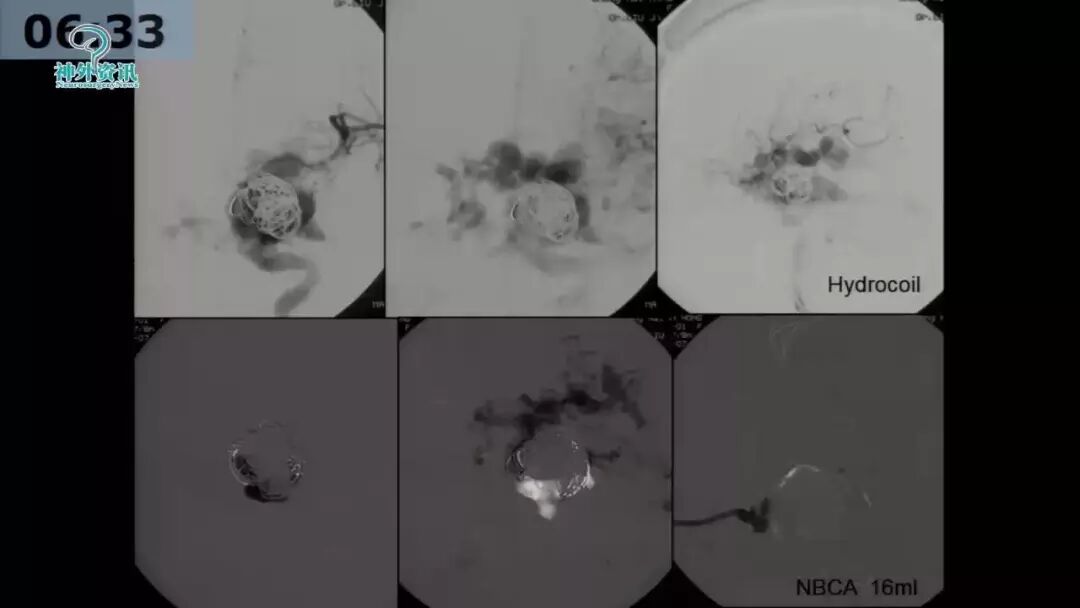

许奕教授:海绵窦区脑膜动静脉瘘的介入治疗